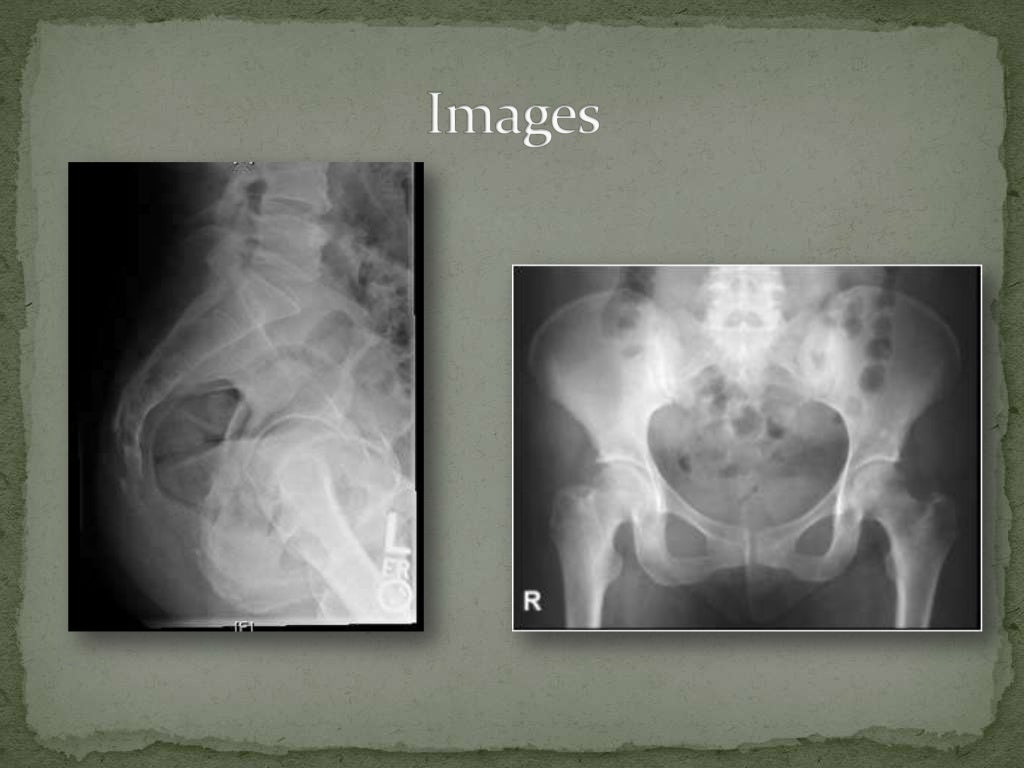

HD Pelvic Fractures EMRAP Tailbone Fracture X Ray Although the treatment may be the same, the recovery time is longer for a. But sometimes the bone itself. Most tailbone injuries are caused by a seated fall or direct blow. Commonly, coccydynia (coccygodynia) occurs after trauma and appears with normal imaging features at static neutral radiography, but dynamic imaging with standing and seated lateral radiography may reveal pathologic coccygeal. Tailbone Fracture X Ray.